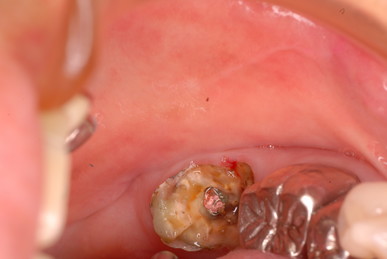

お口の中には高価なセトモノや金歯が多いのですが、

残念ながら健康になったわけではないのです。

分岐部の歯周病を見逃した為に頬が腫れあがり診察の結果、

歯の歯折か重症の分岐部の歯周病と判断した患者さんです。

検査の為に歯茎を開き少し悪いところを取って様子を見ていたのですが、又激痛が走りその為応急処置として東洋医学で対処しました。

ですが、根本的に悪いところを取らなくては再発するだけでなく歯そのものが駄目になる事をお話しして納得してもらい、セラミックを外しその後重症の分岐部の歯周病と判断して歯の一部分と悪い病気の歯肉をえぐりとったその後1週間後の写真です。

DSC_0012右上の奥から2番目の歯が問題の歯です。

セトモノが入っていますが、だからと言って健康になったわけではないのです。切り取った歯の残りと切り取り後が痛々しいですね。